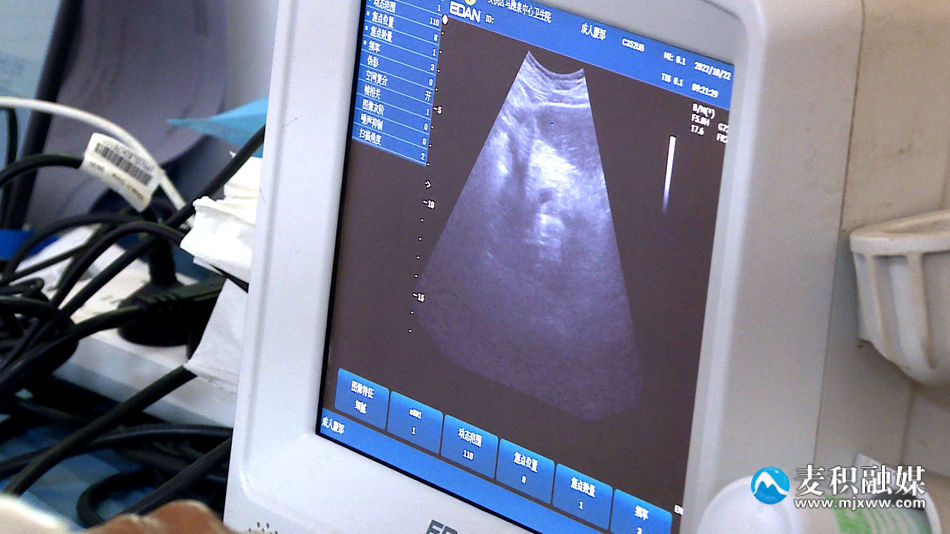

体检中,医务人员与老人亲切交谈,详细询问老人的身体状况、既往病史,并为老人讲解日常保健注意事项。据了解,此次体检的项目包括测量血压、血检、尿常规、心电图、B超等。体检结束后,医务人员将根据检查结果,及时做好老年人和慢性“四病”人群健康体检结果收集、整理、反馈工作,并将体检结果反馈给本人;针对老年人普遍存在的高血压、糖尿病等慢性病给出健康意见,让老年人了解自己的身体健康状况,帮助引导其建立文明健康的生活方式,提高其健康水平和抵御疾病风险的能力。